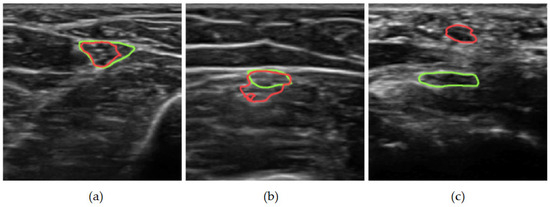

Deep Learning-Based Segmentation of the Ulnar Nerve in Ultrasound Images

by Matthew Bailey Webster, Ko Eun Kim, Yong Jae Na, Joonnyong Lee and Beom Suk Kim

Medicina 2026, 62(1), 113; https://doi.org/10.3390/medicina62010113 - 5 Jan 2026

Background and Objectives: We evaluate deep learning-based segmentation methods for detecting the ulnar nerve in ultrasound (US) images, leveraging the first-ever large US dataset of the ulnar nerve. We compare several widely used segmentation models, analyze their performance, and evaluate several common [...] Read more.

Background and Objectives: We evaluate deep learning-based segmentation methods for detecting the ulnar nerve in ultrasound (US) images, leveraging the first-ever large US dataset of the ulnar nerve. We compare several widely used segmentation models, analyze their performance, and evaluate several common data augmentation techniques for the US. Materials and Methods: Our analysis is conducted on a large dataset of 4789 US images from 545 patients, with expert-annotated ground-truth segmentations of the ulnar nerve, and uses six segmentation models with several backbone architectures. Further, we analyze the statistical significance of five common data augmentation techniques on segmentation performance: flipping, rotation, shearing, contrast and brightness adjustments, and resizing. Results: In this study, the shear, rotate, and resize augmentations consistently improved segmentation performance across multiple runs, with p-values < 0.05 in a paired t-test relative to the no-augmentation baseline. Furthermore, we showed that newer architectures do not provide any metric improvements over traditional U-Net models, which achieved a Dice score of 0.88 and an IoU of 0.81. Conclusions: Through our systematic analysis of segmentation models and data augmentation strategies, we provide key insights into optimizing deep learning approaches for ulnar nerve segmentation and other US-based nerve segmentation tasks. Full article